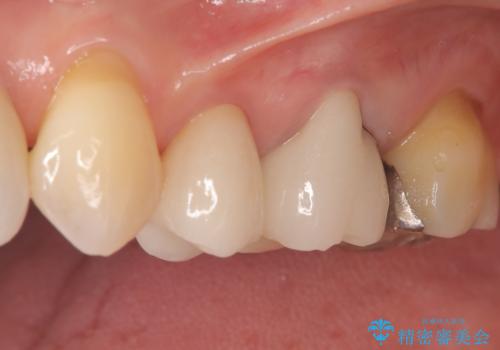

- 「以前治療した被せ物の色が気になる」「最近しみるようになった」との主訴で来院されました。診察の結果、古い被せ物の周囲に段差ができており、そこから虫歯が進行している状態でした。また、色も経年劣化により周囲の歯と調和が取れておらず、笑ったときに目立つとのお悩みもありました。

被せ物の下の虫歯を除去し、必要に応じて土台の補強を行ったうえで、見た目が自然で長期的な安定性もあるセラミッククラウンによる修復をご提案しました。見た目と機能の両方を改善するため、隣接する歯との色調や形態のバランスも考慮した治療計画を立てました。

まず古い被せ物を慎重に取り除き、中に広がっていた虫歯を丁寧に除去しました。歯質の状態を確認したうえで、必要な部分には土台(コア)を補強し、セラミッククラウンを装着する準備を整えました。

最終的な被せ物には、周囲の歯と自然になじむような色合い・透明感を持つセラミックを採用。形も元の歯に近づけ、違和感のない見た目と噛み心地を再現しました。